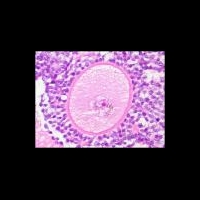

В качестве объекта исследования были выбраны ткани яичника, удаленного у 20-летней женщины. Исследователи выделили в яичнике стволовые клетки, содержащие на своей поверхности специфический протеин DDX4. Выделенные стволовые клетки были помечены зеленым флуоресцентным белком.

Ученым удалось зафиксировать в лабораторных условиях процесс овогенеза: в течение двух недель из меченых стволовых клеток развились ооциты – незрелые яйцеклетки.

На следующем этапе исследования ооциты были возвращены в ткани яичника, и учитывая требования в адекватном кровеснабжении, вживлены под кожу живой мыши.

Под кожей живой мыши ооциты полностью созрели и превратились в зрелые яйцеклетки. Ученые сообщили о полном совпадении по своим функциональным характеристикам между полученными яйцеклетками и яйцеклетками, образующимися в женском организме естественным путем.